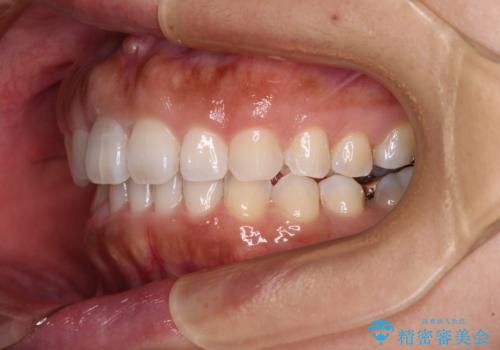

隙間の空いた前歯を閉じたい インビザライン矯正

- 前歯の隙間を気にして来院された患者様です。

隙間、捻転ともに軽微でありましたが、下顎前歯の突き上げにより隙間ができていたため、インビザラインを用いて咬み合わせを改善しながら前歯の歯列を整えていくこととしました。

当初は1年程度で終えられると思いましたが、治療途中から装着時間が短くなったり、来院間隔が長期になったりとし、結果として4年半以上の治療期間となりました。

治療途中に上顎前歯は失活してしまいましたが、変色が顕著ではないため、経過を見ていくこととなりました。